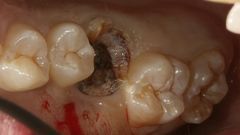

例(23歳男性)をあげますと

虫歯で抜かないといけない歯があります(大きく穴があいた歯)。

その奥に噛み合わせに関係ない親知らずがあります(一番右端の歯)。

虫歯の歯を抜いて、親知らずを移植しました。

傷が治って問題なく噛めるようになりました。